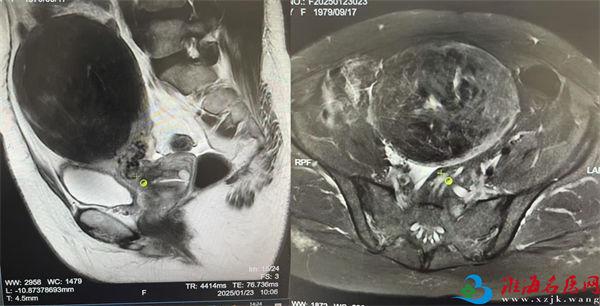

据刘阳主任介绍,45岁患者李女士是一位教师,体检发现如此巨大的子宫肌瘤后十分忧心,寒假初始便到院就诊。彩超显示肌瘤最大直径已达11厘米,核磁显示可见瘤体已占据大部分盆腹腔。因李女士工作繁忙,只能趁着短暂的寒假手术,并希望尽快恢复。同时为避免肌瘤复发,患者征求医生意见,是否可以切除子宫。刘阳主任在与患者充分沟通后,决定为患者采取超微创的“单孔腹腔镜技术”为其进行手术。

面对如此巨大的瘤体实施单孔腹腔镜有不小技术难度,刘阳主任与团队人员术中在患者肚脐正中做一个2cm小切口,实施单孔腹腔镜操作,切除子宫及瘤体后,从脐部小切口旋切取出,为其成功实施了单孔腹腔镜全子宫切除手术。术后第3天,患者即达到出院标准。术后回访,李女士也表示自己的身体现在恢复的非常好。